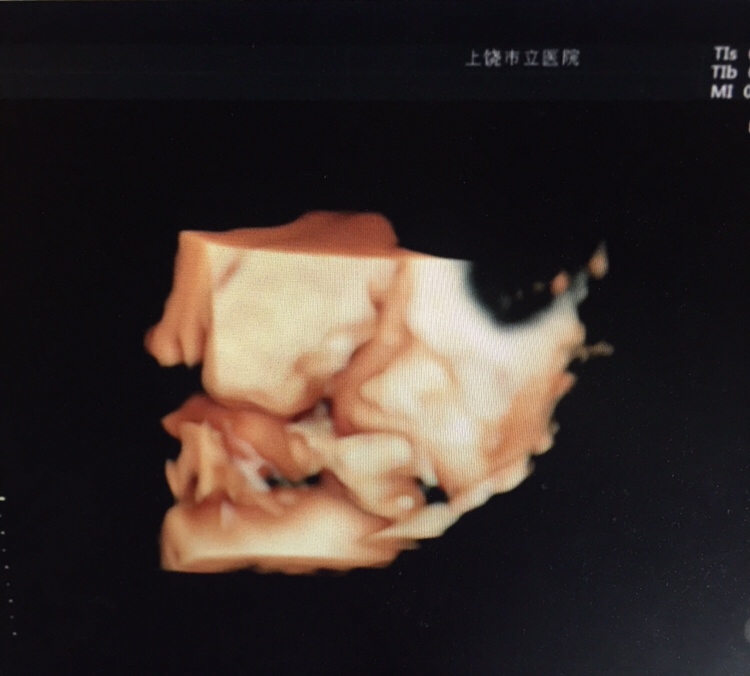

孕10周+5天